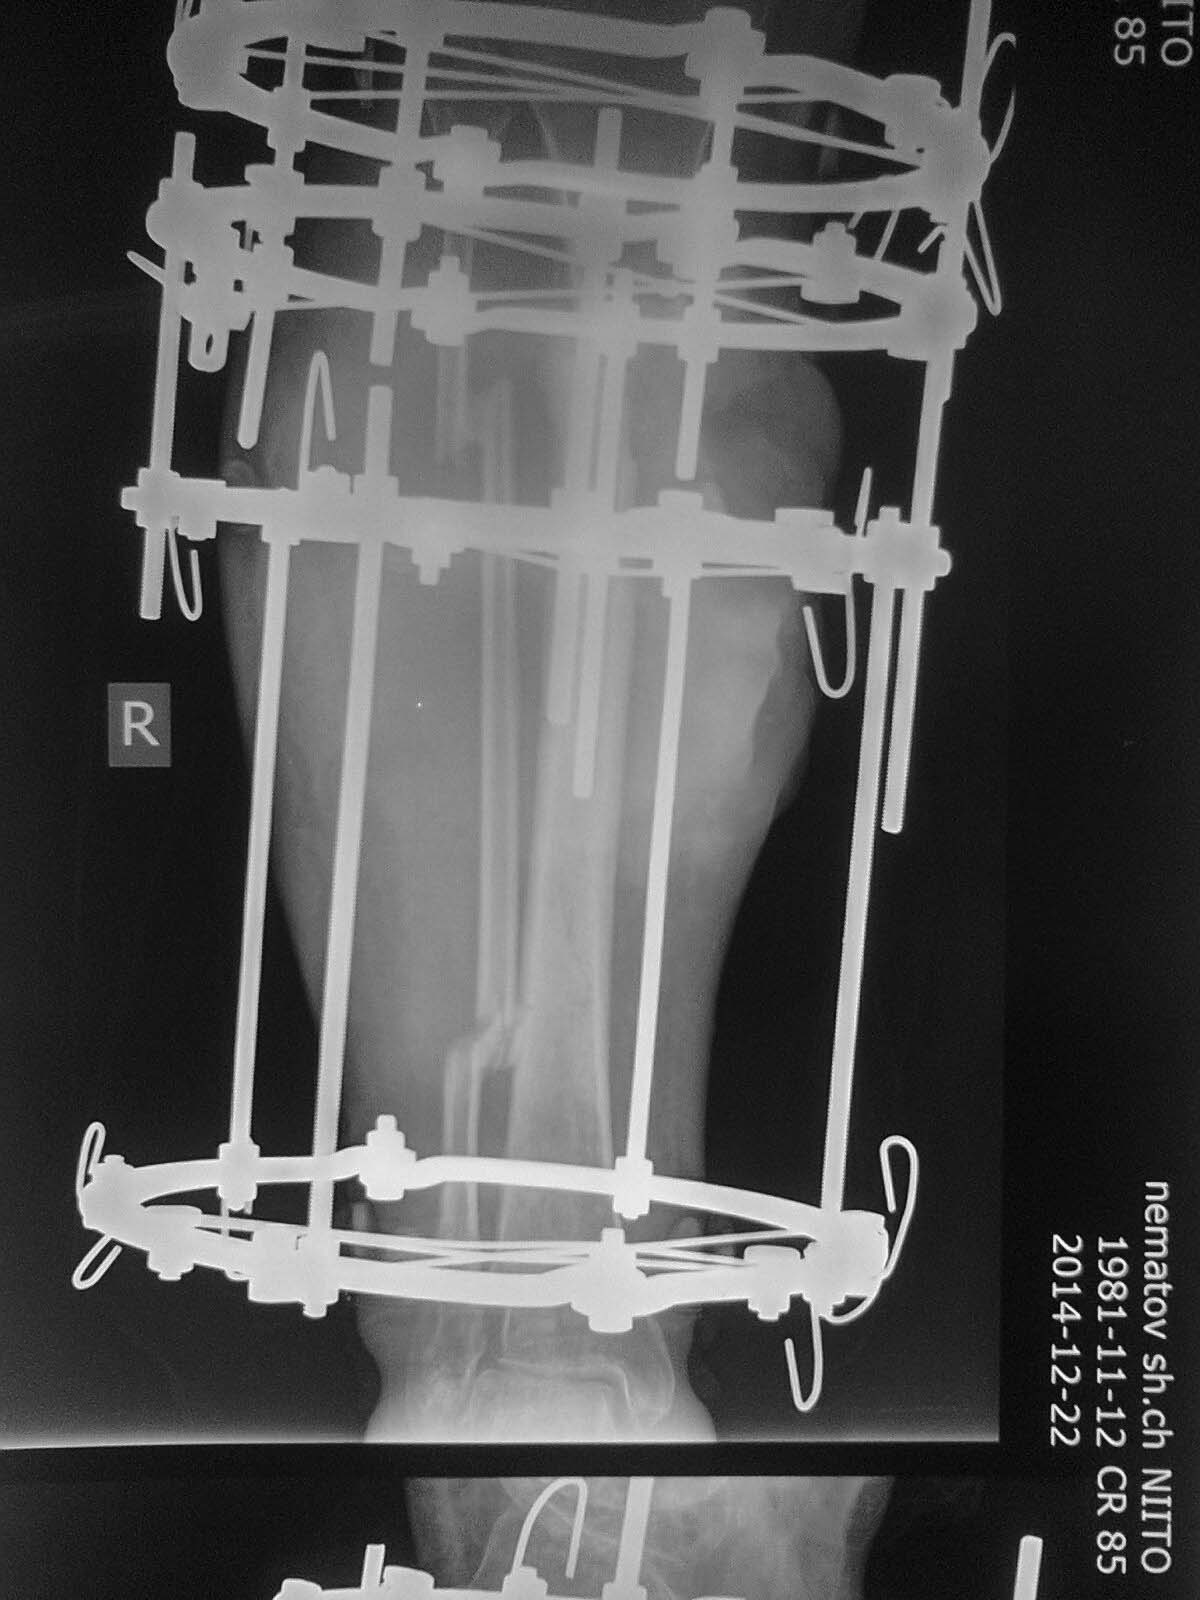

Выполнено: остенекрсеквестрэктомия, резекция концов отломков, перемонтаж

аппарата (фото 2). Рана успешно зажила, пациент исчез из вида.